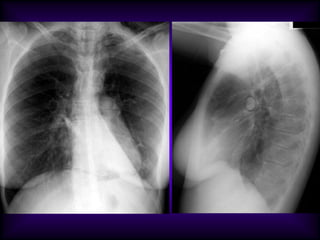

Necrotizing Pneumonia / Lung Abscess / Aspiration

Superior segment RLL dense pneumonia

Progression / Cavity